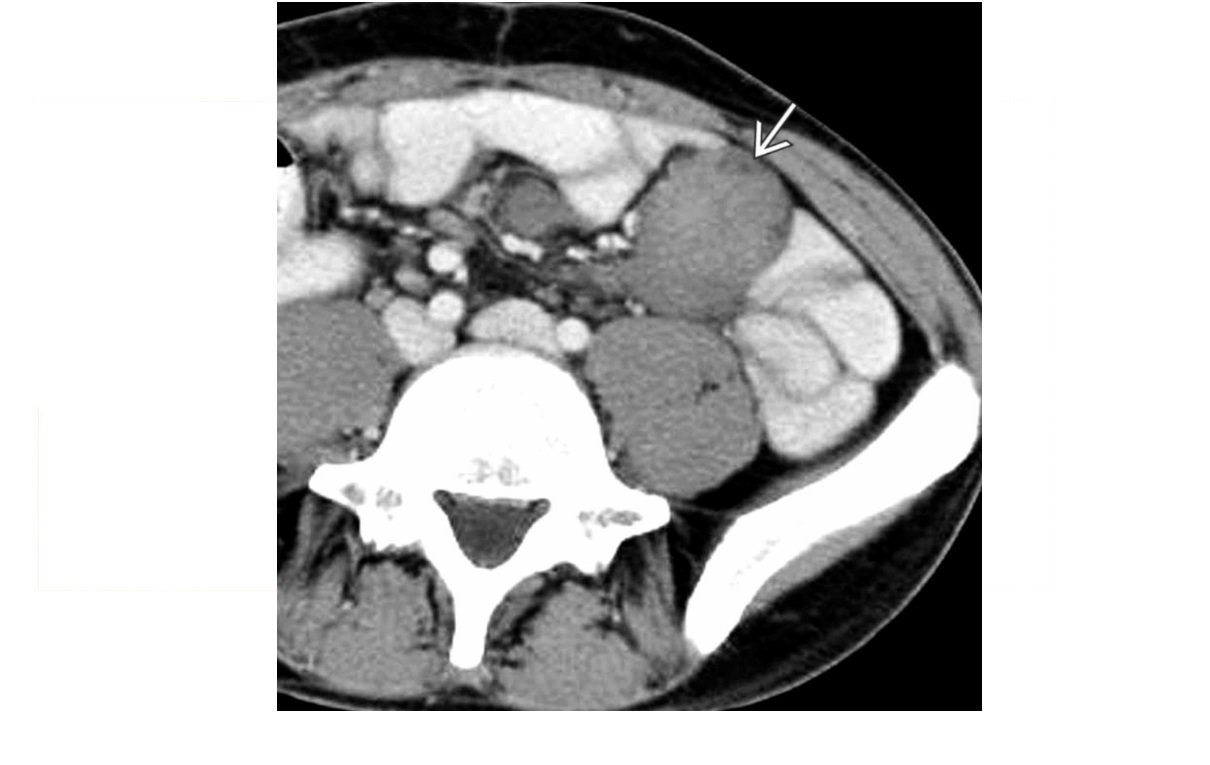

CT enterography features of active Crohn’s disease

**mucosal hyperenhancement **- most sensitive indicator but seen in other bowel diseases most specific sign for chrons - **Prominence of the vasa recta adjacent to the inflamed loop of bowel (comb sign) along with increased mesenteric fat attenuation** wall thickening (thickness >3 mm) CT enterography to depict extra-enteric disease/complications including -obstruction -sinus tract -fistula and abscess formation long-standing/inactive features include -submucosal fat deposition -pseudosacculation -surrounding fibro-fatty proliferation -fibrotic strictures MR enterography and enteroclysis - MR enteroclysis was superior to MR enterography in demonstrating mucosal abnormalities. -MR enteroclysis better bowel distension but not necessarily better diagnostics -MR enterography is more acceptable to the patient than MR enteroclysis